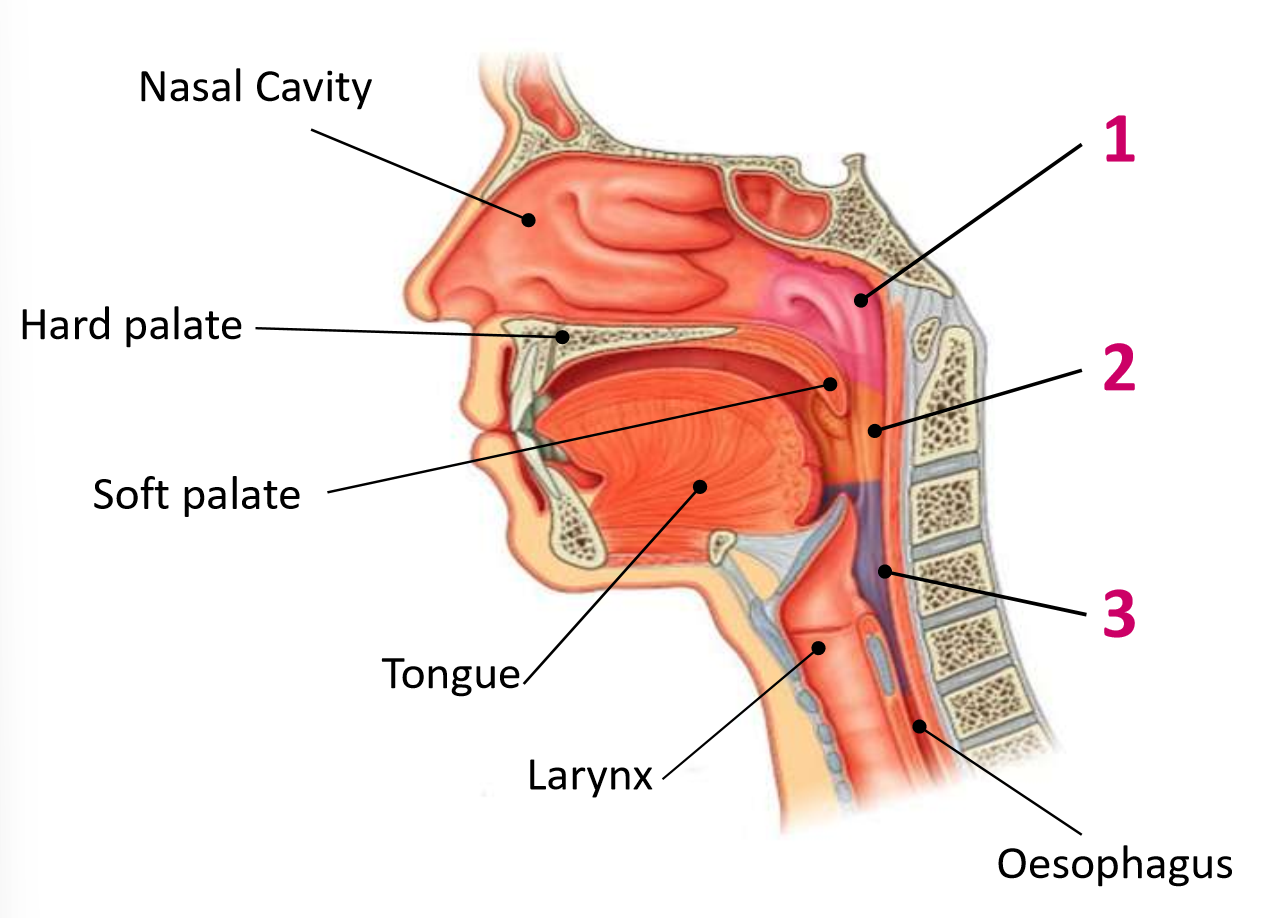

Which area of the head and neck do 1, 2, and 3 make?

pharynx

What region is 1?

nasopharynx

What region is 2?

oropharynx

What region is 3?

laryngopharynx

What is the anterior wall of 1?

posterior nasal choanae

What is the roof of 1?

body of sphenoid and basilar part of occipital

What is the posterior wall of 1?

anterior arch of atlas covered in pharyngobasilar fascia

What is the floor of 1?

soft palate

What is the anterior wall of 2?

oropharyngeal isthmus

What is the roof of 2?

soft palate

What is the floor of 2?

pharyngeal part of tongue and glossoepiglottic fold

What is the posterior wall of 2?

C2 and upper C3

What are the lateral walls of 2?

palatoglossal and palatopharyngeal arches